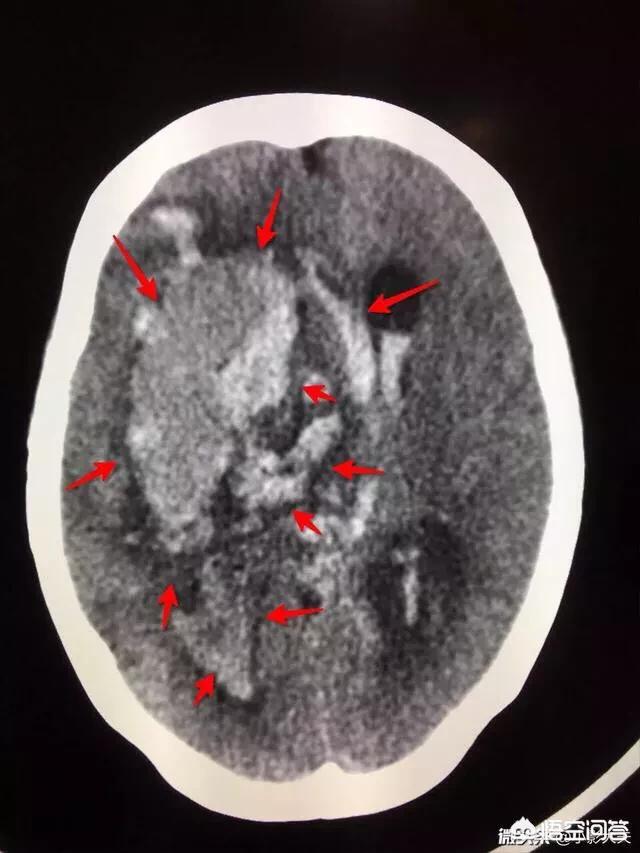

高血圧性脳症、脳出血臨床では、高齢者がめまいや頭痛を訴えて受診し、CTで大脳基底核部に脳出血が見つかった場合、その8割に高血圧の既往があり、高血圧とわかっていてもコントロールできていなかったり、薬を1日飲んで数日やめたりする患者さんがほとんどです。これまでで最も若い高血圧性脳出血は30歳で、高血圧であることは知っていたが、自分は若いから大丈夫だろうと思い、治療を受けなかった。

農業を営む75歳のおばあちゃん。午前8時15分、トイレで意識を失って倒れているのを発見された。緊急入院となり、血圧を測定したところ233/122mmHg(正常値140/90)であった。高血圧の既往があり、1年間降圧剤を服用していなかった。CTでは、少なくとも200mL以上の頭蓋内出血、脳幹出血、脳室出血、脳ヘルニアが認められた。脳は血でいっぱいだった。病状は非常に重く、予後が悪いことを家族に伝えた結果、家族は治療を断念することにした。